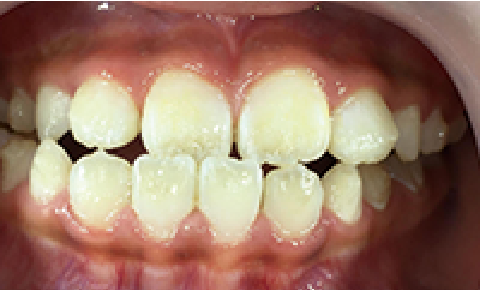

症例 : 7歳 女性

Before

After

主訴

叢生(歯がガタガタ)

治療方法

床矯正+インビザラインファースト

総額治療費

550,000円(税込)

治療期間

3年

治療のリスク・副作用

前歯を正しい位置に移動する時に、咬み合わせが不安定になることがあります。

改善ポイント

左側の前歯が反対咬合のため、床矯正だけでは改善が難しく、インビザラインファーストを併用しました。

少しずつ動かしていく必要があるため、治療期間もやや長くかかりましたが、綺麗な歯並びになりました。